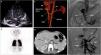

Some tests were performed to find the cause of hypoxemia. No evidence of pulmonary hypertension nor of intracardiac shunts were noticed on echocardiography with agitated serum, but quick pass of microbubbles to the left atrium was suggestive of an intrapulmonary shunt (Fig. 1A, Video 1). No lung disease and no evidence of macroscopic pulmonary arterio-venous fistulas were detected in the thorax angio Computed Tomography (CT). However, under the suspicion of an extra-cardiac right to left shunt, a lung nuclear scanning with Technetium 99m-labeled macroaggregated albumin was requested. Brain and kidney radiotracer uptake confirmed the presence of a right to left shunt of 36% (Fig. 1B). These findings were indicative of an intrapulmonary shunt suggestive of hepatopulmonary syndrome. An abdominal echography demonstrated a porto-caval latero-lateral shunt with a well-developed portal vein system. An abdominal angio-CT confirmed the diagnosis of Abernethy type-2 malformation (Fig. 1C and D).

(A) Echocardiography. Four chamber view depicting a shaked serum. After three cardiac cycles the left atrium was also opacified. (B) Nuclear scanning with Technetium 99m macro-aggregated albumin. A part from the lungs, brain and kidney also showed radioactivity due to tracing uptake (red circles). (C) CT Angiogram. 3D Volume rendering showing the Abernethy malformation. (D) CT Angiogram: Axial plane illustrating the Abernethy shunt (red arrow). (E) Fluoroscopy. Left oblique projection. The centimetered catheter reaches the portal vein from the inferior vena cava, through Abernethy shunt (asterisk). (F) Fluoroscopy. Antero-posterior projection. Balloon shunt occlusion test. Abbreviations: Abd Ao: abdominal aorta. IMS: inferior mesenteric vein. IVC: inferior vena cava. LA: left atrium. PV: portal vein. RA: right atrium. SMV: superior mesenteric vein. SP: splenic vein.

The case was presented to an interventional radiology team of the reference hospital. A catheterization procedure documented a 10mm side-to-side shunt between the portal vein and the inferior vena cava (IVC) (Fig. 1E). The basal portal vein and IVC pressures were 9 and 3mmHg, respectively, and a balloon shunt occlusion test evidenced a moderate increase in portal pressure up to 23mmHg (Fig. 1F). The anatomic (broad and short) shunt morphology was not suitable for any endovascular device. Therefore, the patient was presented to the pediatric hepato-digestive surgery team and underwent a surgical shunt closure through laparoscopy using a hem-o-lok® clip system. Thereafter the patient followed a favorable clinical course. Liver function and liver blood flow were monitored daily through blood test and echography, and remained normal. Before patient discharge, hypoxemia persisted with a basal transcutaneous hemoglobin saturation of 90% and, hence, a home oxygen therapy with nasal cannula (3L/min) was provided. During follow-up the patient experienced a progressive improvement of his hypoxemia and six months after shunt closure oxygen therapy was withdrawn.